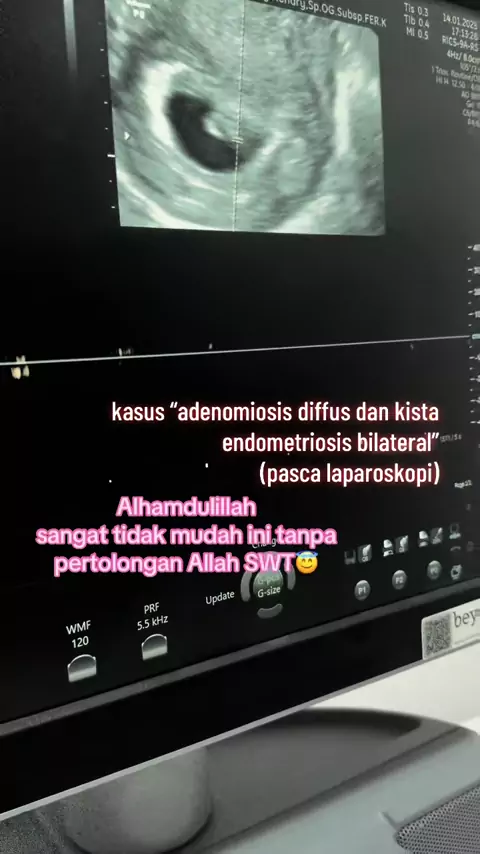

perjuangan berat ini😇 laparoskopi dulu membuang adenomiosis diffus dan kista endometriosis bilateral, terapi hormon, bayi tabung, ultra long protocol FET.. Alhamdulillah Allah menurunkan pertolongan Nya.. Allah maha kuasa. makhluk tak kuasa” @klinikdesani @Morula IVF Padang

musuh terberat kesuburan adalah Adenomiosis dan kista endometriosis… Alhamdulillah bisa hamil lagi beberapa pasien kita semua atas ijin dan kuasa Allah.. alhamdulillah @klinikdesani @Morula IVF Padang #endometriosis #adenomiosis #inseminasiintrauterine #edukasidokterdedy #praktekdokterdedyhendry